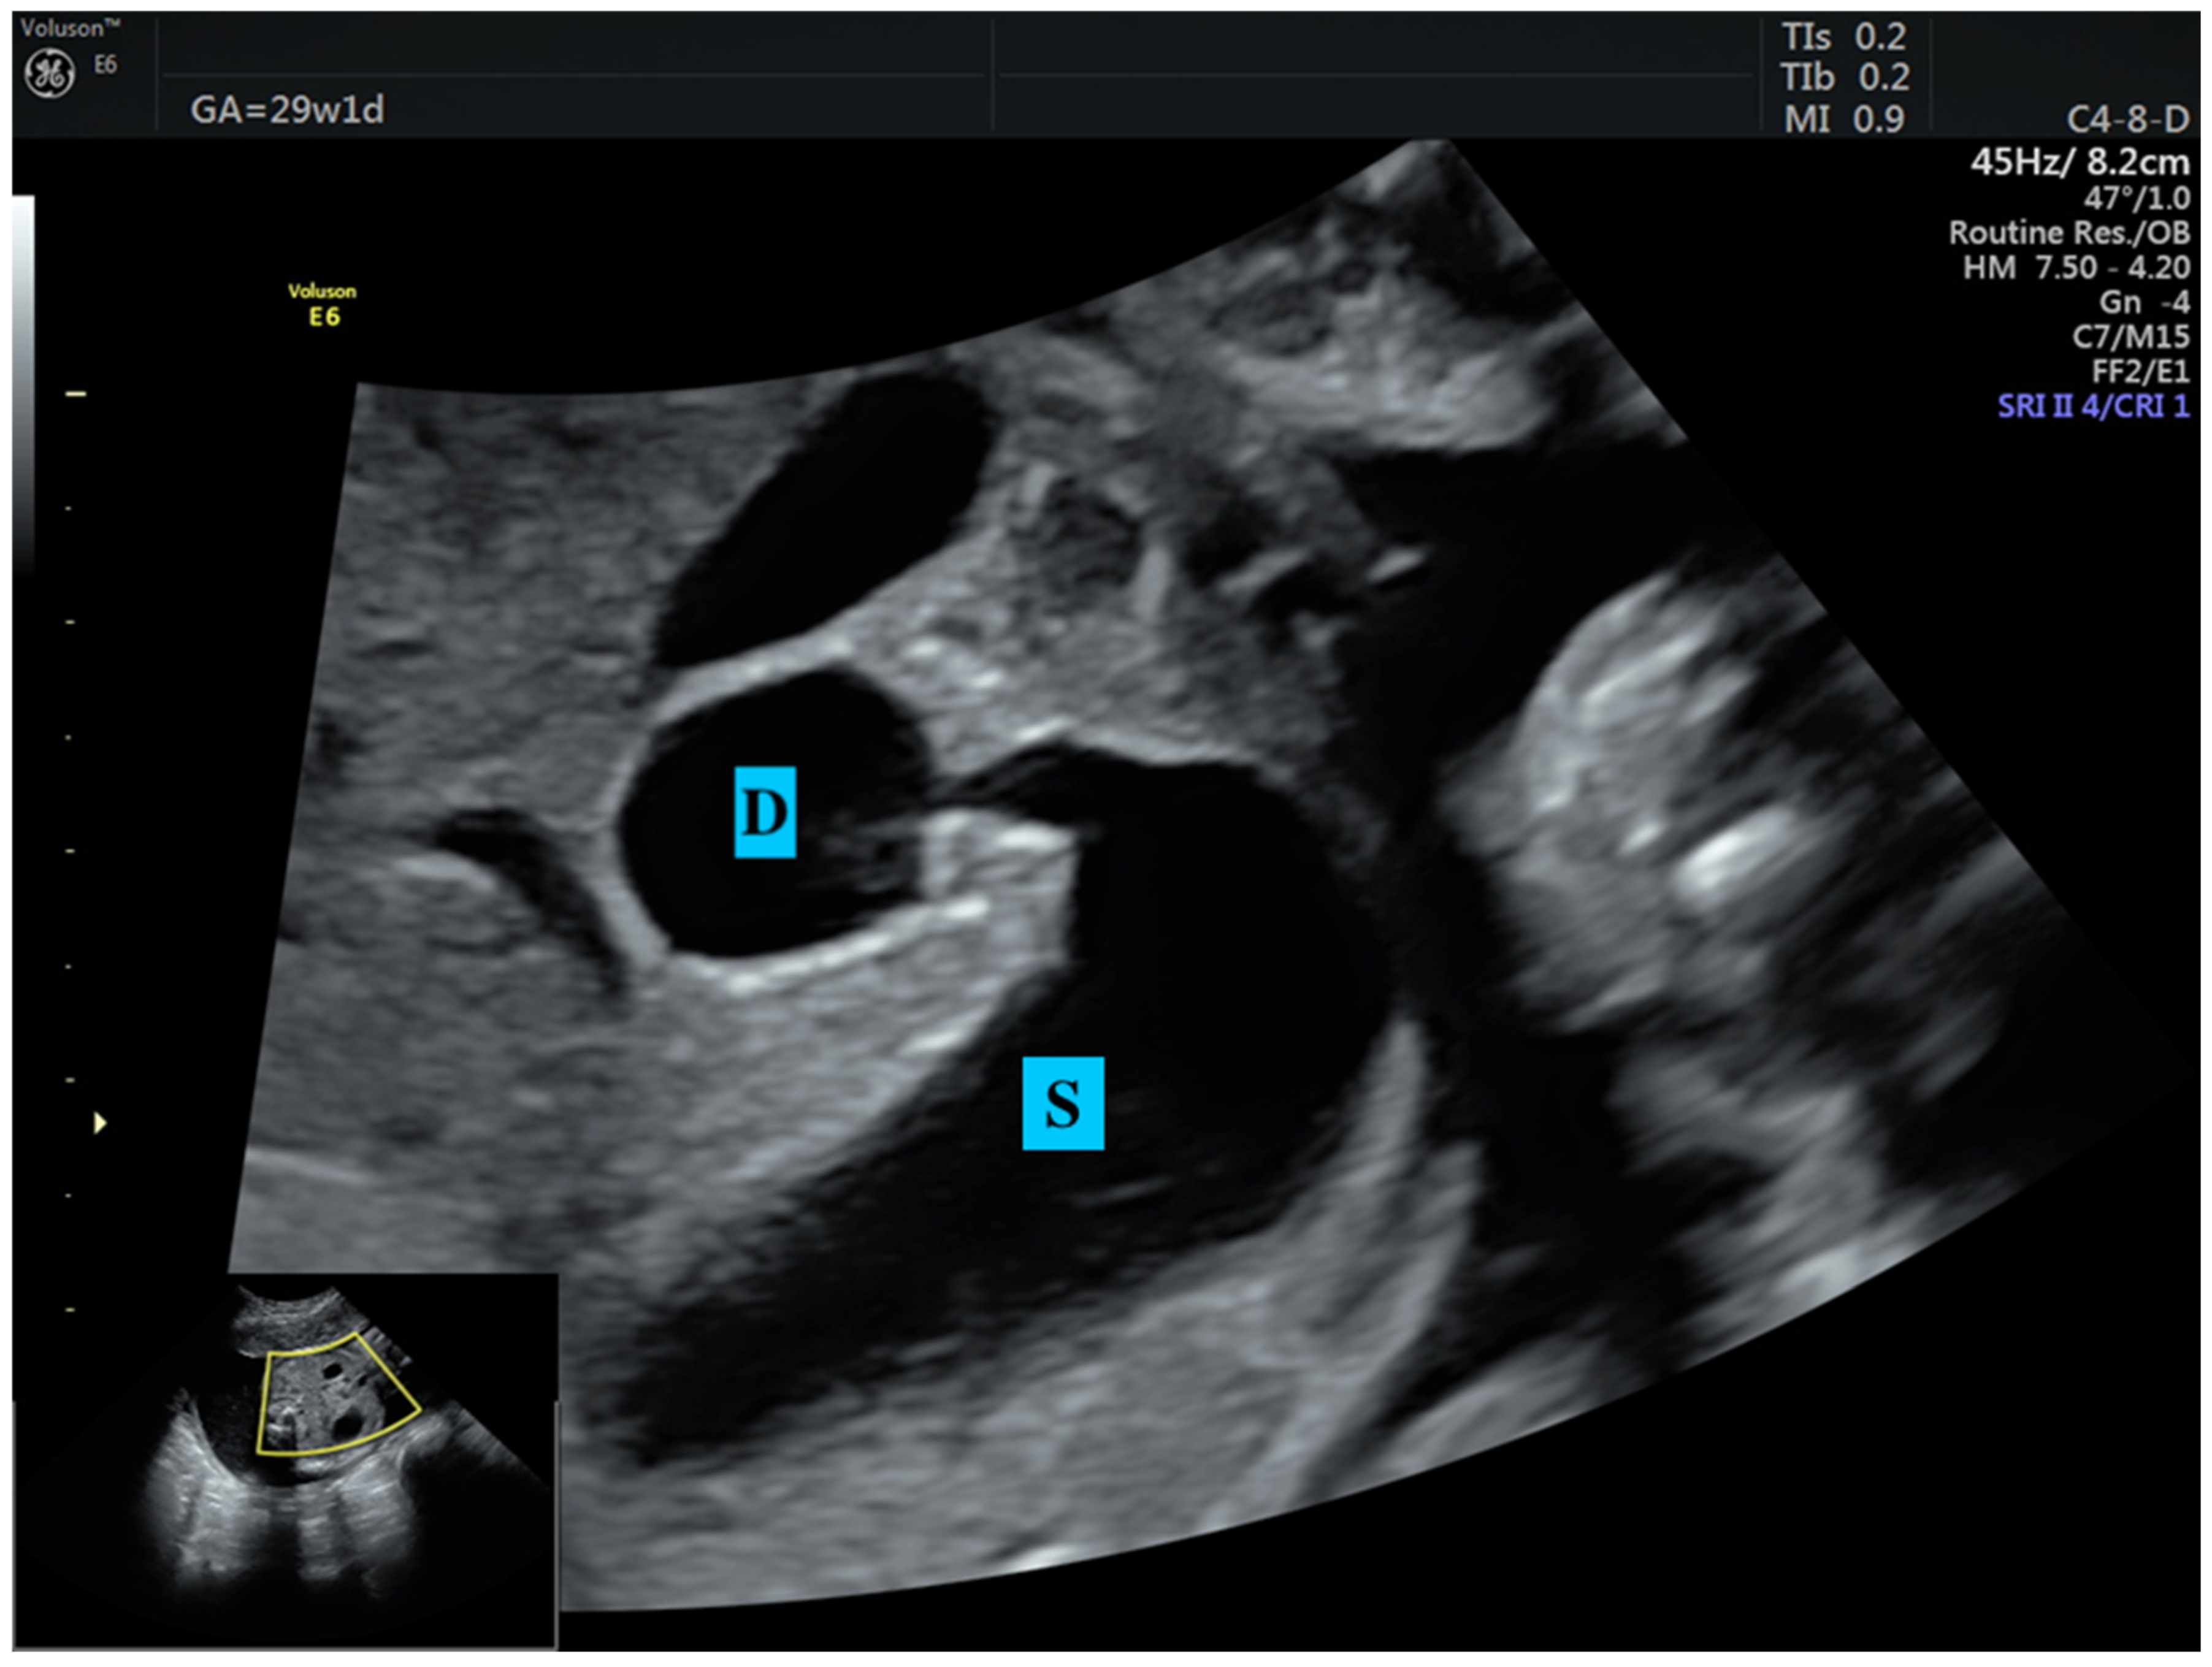

- Dankovcik, R.; Jirasek, J.E.; Kucera, E.; Feyereisl, J.; Radonak, J.; Dudas, M. Prenatal diagnosis of annular pancreas: Reliability of the double bubble sign with periduodenal hyperechogenic band. Fetal Diagn. Ther. 2009, 24, 483–490. [Google Scholar] [CrossRef] [PubMed]

- Yin, C.; Tong, L.; Ma, M.; Tan, X.; Luo, G.; Fei, Z.; Nie, D. The application of prenatal ultrasound in the diagnosis of congenital duodenal obstruction. BMC Pregnancy Childbirth 2020, 20, 387. [Google Scholar] [CrossRef]

- Zhang, B.; Zhang, W.; Hu, Y.; Pang, H.; Yang, H.; Luo, H. Evaluation of prenatal and postnatal ultrasonography for the diagnosis of fetal double bubble sign. Quant. Imaging Med. Surg. 2024, 14, 6386. [Google Scholar] [CrossRef]

- Demirci, O.; Eriç Özdemir, M.; Kumru, P.; Celayir, A. Clinical significance of prenatal double bubble sign on perinatal outcome and literature review. J. Matern.-Fetal Neonatal Med. 2022, 35, 1841–1847. [Google Scholar] [CrossRef] [PubMed]

| Double bubble sign (n, %) | 13 (100) | 17 (100) | N/A |

| Dilated stomach (n, %) | 13 (100) | 17 (100) | N/A |